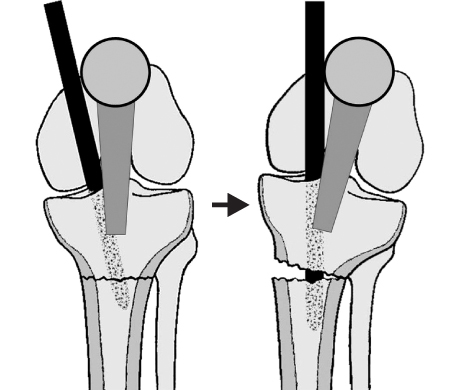

Fig. 8

(A, B) Initial radiographs show the proximal tibial fracture at the proximal meta-diaphyseal junction.

(C, D) Postoperative radiographs show good alignment of the fracture fixed with a locked tibial nail and blocking screws to prevent malalignment. A blocking screw was placed lateral to the central axis to prevent valgus angulation and the other blocking screw was placed posterior to the central axis to prevent apex anterior angulation.